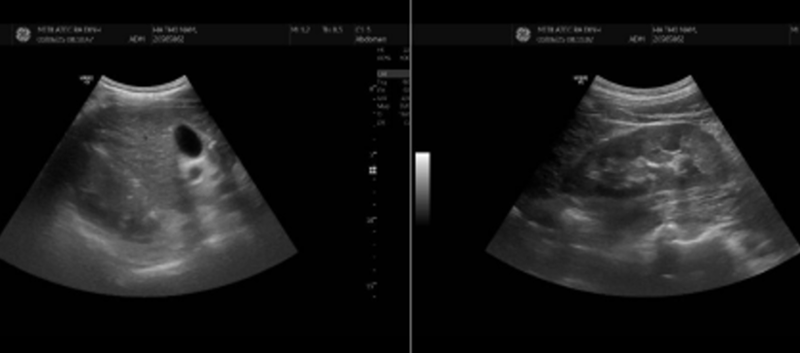

Kết quả siêu âm tổng quát có đàn hồi mô gan cho thấy hình ảnh nhu mô gan thô, bờ không đều

Kết quả siêu âm tổng quát có đàn hồi mô gan cho thấy hình ảnh nhu mô gan thô, bờ không đều (theo dõi xơ gan). Độ cứng của gan tương đương F4 (theo Metavir-LB).